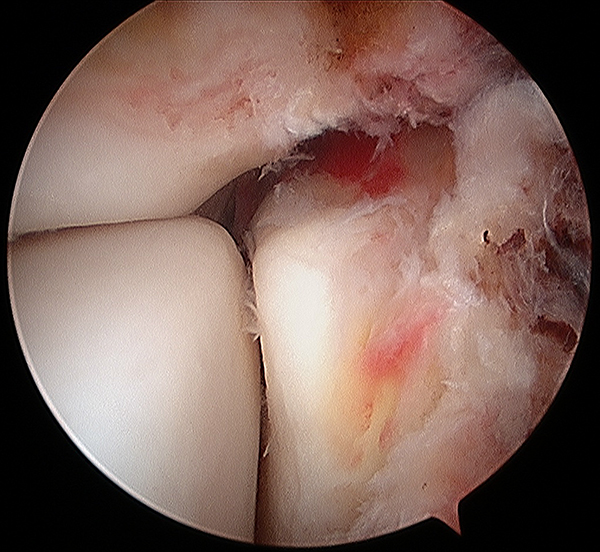

Luego se procede a realizar la reducción y osteosíntesis de las lesiones óseas (primero peroné y si existe luego la fractura del maléolo medial). En 8 casos que presentaban lesión del ligamento deltoideo se realizó la colocación de un arpón en el astrágalo con suturas transfixiantes en maléolo medial para cerrar el espacio. En dos casos con fractura del maléolo tibial, se observó artroscópicamente la presencia de tejidos de partes blandas interpuestos en el foco fracturario. Luego se continuó con la reducción manual más fijación de la sindesmosis con sutura con endobotón y finalmente se constata mediante radioscopia y artroscopía la correcta reducción de la articulación (figs. 4 y 5). En dos procedimientos, se observó artroscópicamente que la reducción no era la adecuada, por lo que se mejoró la tensión del sistema (button) y se corroboró la corrección por visualización artroscópica.

Figura 4: Diastasis previa reducción con sistema de Button ajustable para lesiones de la sindemosis.

Figura 5: Control artroscópico de la articulación reducida.